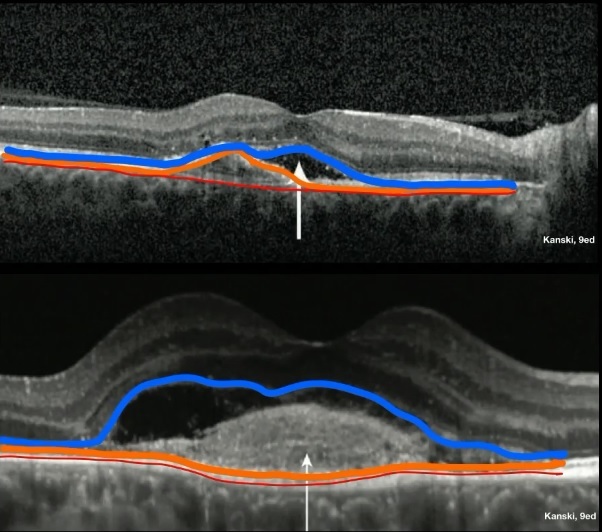

Como podemos classificar as NVC através do OCT?

NVC Tipo I: abaixo do EPR

NVC Tipo II: entre a retina e o EPR

NVC Tipo III (Proliferação Angiomatosa da Retina)

Conecta o Plexo Capilar Profunda da retina com a coróide.

O que é o DEP Drusenoide?

DEP Drusenoide ocorre quando temos a confluência de drusas moles, levando à um descolamento do EPR > 1000 micrômetro (CBO) OU > 350 micrômetros (AAO).

Quais são os achados típicos das drusas no OCT?

Elevações da Linha do EPR, separando-a de outra linha hiperrefletiva: a Membrana de Bruch